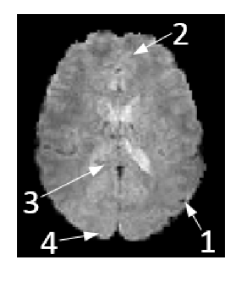

To understand the rationale behind this modeling, Fig. 1 shows 4 timecourses of arbitrarily selected pixels in a resting state fMRI dataset, that exhibited high correspondence () with regressors that represent a Default Mode Network (DMN) map or a visual network map after a dual-regression against those network maps. The signals in the figure were extracted from the fMRI sequence after conventional fMRI pre-processing (including skull stripping, motion correction and slice timing correction), and the spatial locations of the selected pixels are shown at the bottom left of the figure. The timecourses are shown in the time domain (top left) and in the temporal Fourier domain, after removing the DC component (top right). It can be seen that while three of the timecourses exhibit peaks in the spectral domain and are suitable for sparse representation in the temporal Fourier domain, one of the timecourses exhibits a broad spectrum in the temporal Fourier domain. As a result, separation into fixed rank and periodic components allows better representation of signals (compared to fixed-rank only or periodic component only) as it is expected to capture both broad-band and band-limited temporal spectra.

Finally, we examined the separation of PEAR into into A and P components, in terms of both time courses and spatial z-stat maps (for R=6.66). For this purpose, we first performed dual regression analysis for the A component and for the P component separately, to generate a z-stat map for each. Those maps, thresholded at and with color scale mapped between , are shown in Fig. 10 and demonstrate that both A and P components contain functional activity. Then, we arbitrary selected a single pixel that exhibited high correspondence with DMN for both A and P (z-stat value of ). Figure 11 shows the timecourses and amplitude spectra of the A and P components, for the selected pixel, where the spatial location of the pixel is shown at the bottom of the Figure. The timecourses and amplitude spectra show that the A component contains a wide range of frequencies, with some strong peaks in the spectrum for frequencies that have strong total energy. The P component contains a limited number of temporal frequencies and captures the low-energy periodicity that is not captured in A. This separation shows that a selection of a fixed, moderate rank for the A component, in addition to a demand for a limited number of temporal frequencies for the P component leads to the desired separation, which results in improved z-stat results shown earlier.